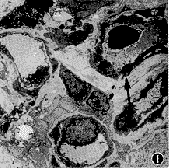

3.透射电镜观察:黄斑下NVM主要由新生毛细血管组成。管壁由血管内皮细胞和周细胞构成,管壁外可见不完整的类似基底膜的成分,管腔内除血浆成分外,偶见白细胞(图1)。在病理切片中可见尚未形成血管腔的内皮细胞和周细胞(图2)。此外,也偶见RPE细胞(图 3)。血管间质充满丝状的血浆沉积物(图4)。

图2 在高倍镜下可见尚未形成管腔的新生血管内皮细胞和胞浆内充满细丝样结构的周细胞(箭头) ×8 000